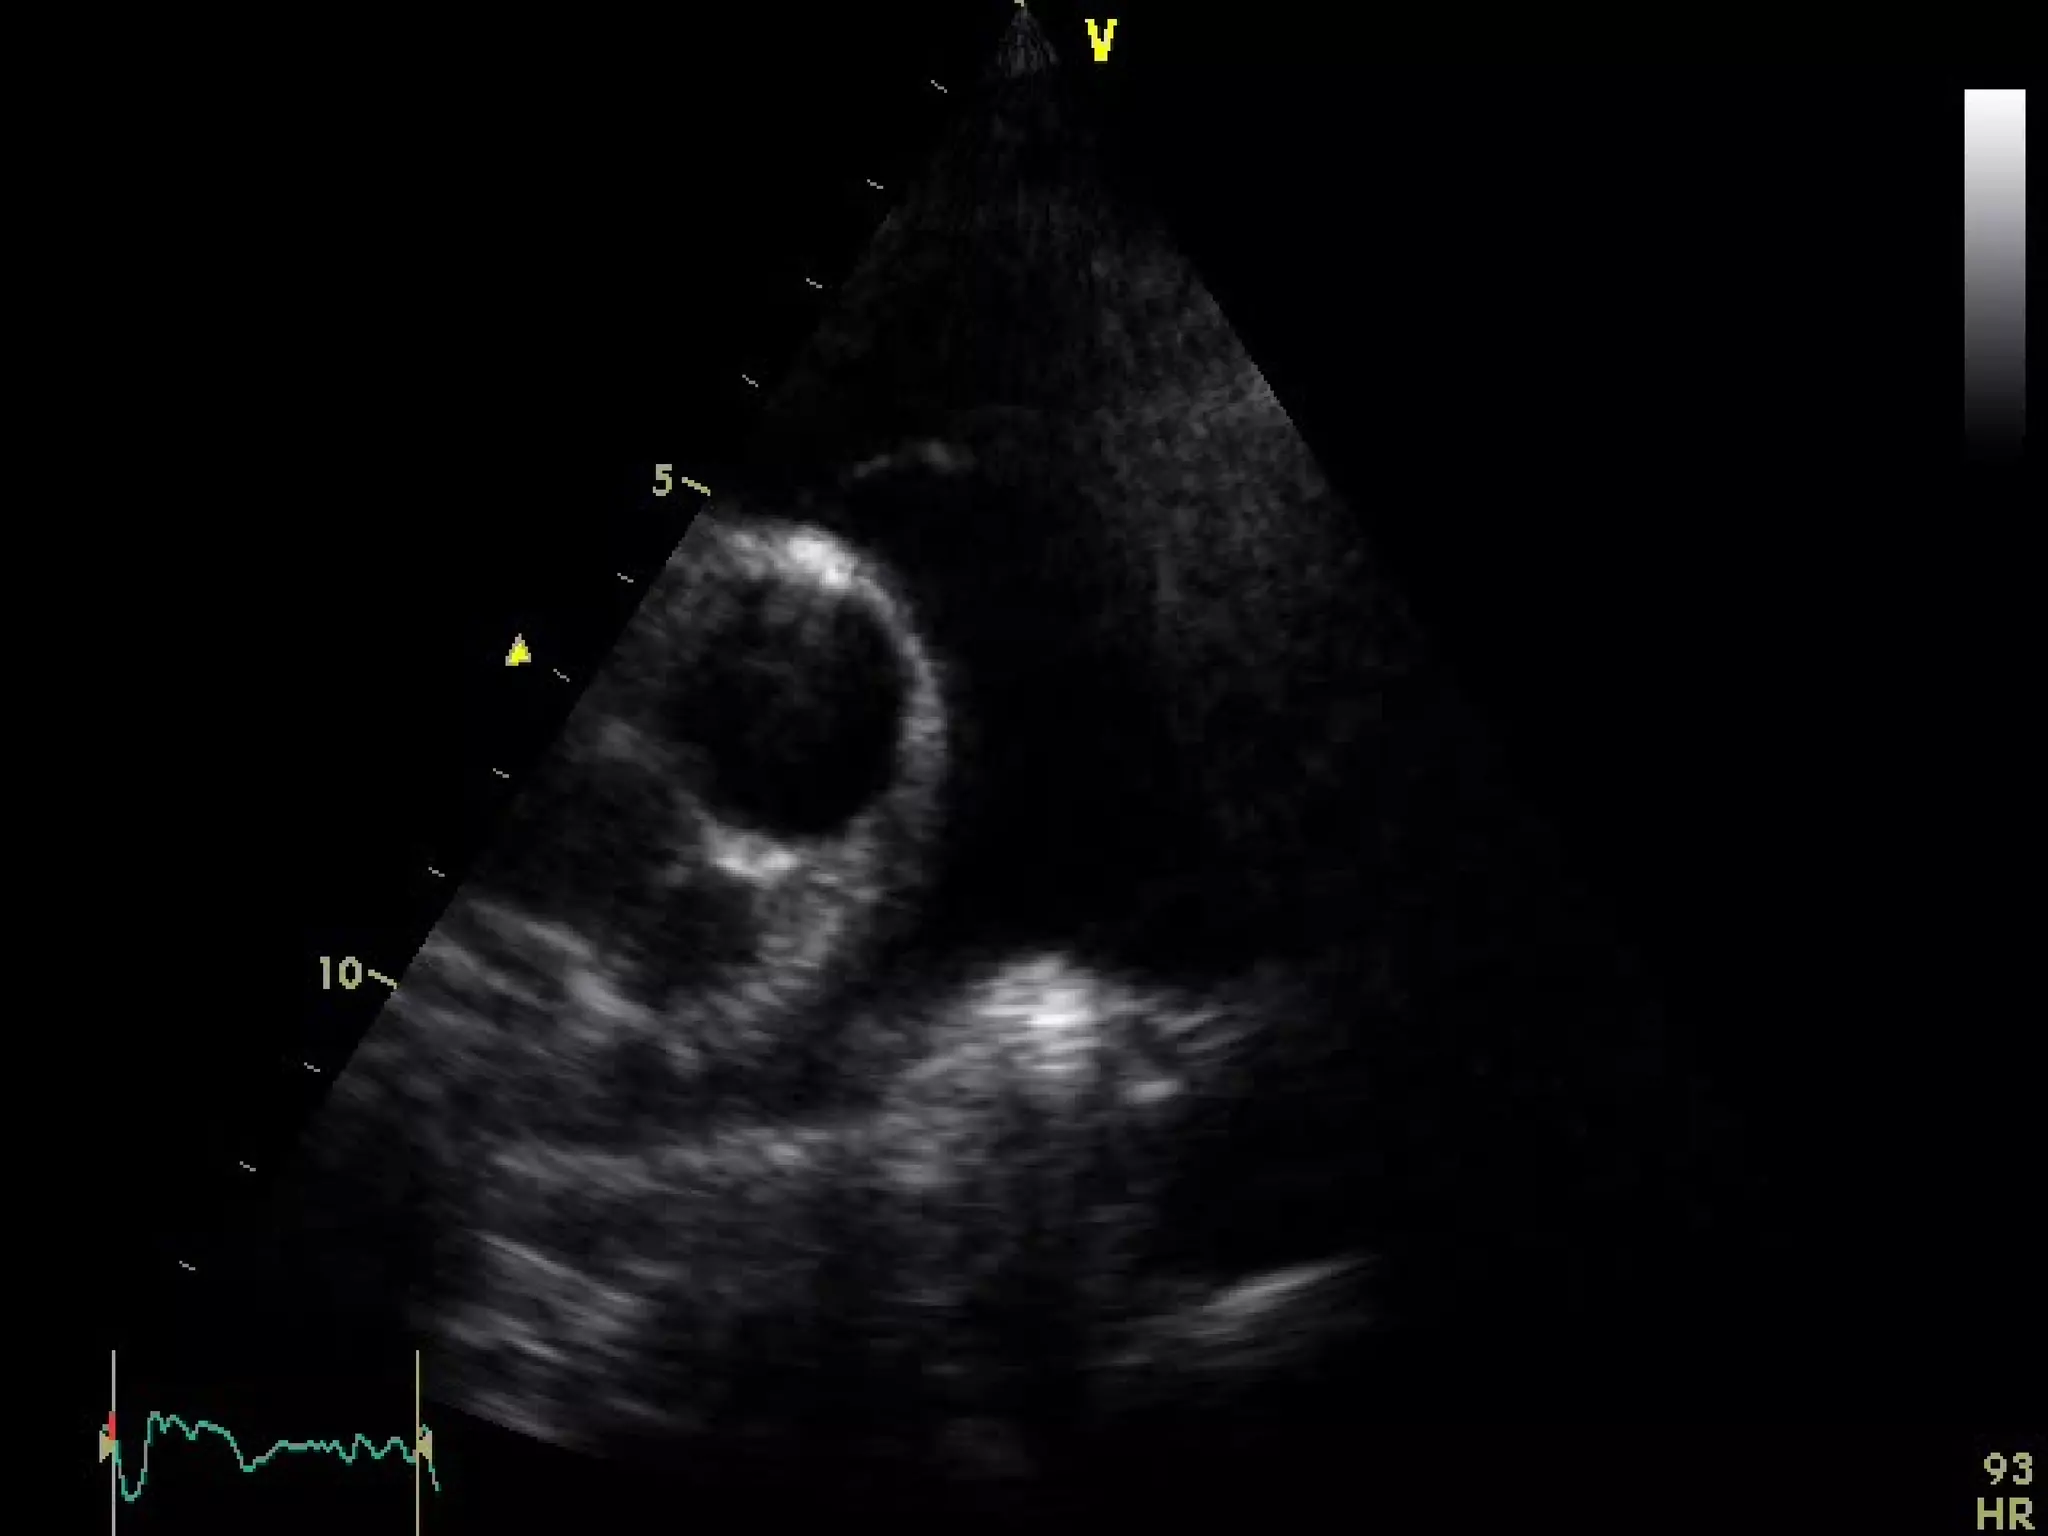

From the PLA orientation, a 90° clockwise rotation of

the transducer with superior and inferior

transducer manipulations permits delineation of the

parasternal short axis (PSA) views:

-At the base (aortic valve) view

-Mid (mitral valve ) view

-Mid ( papillary muscle) view

-And apical levels view

Parasternal short axis

From the PLAorientation, a 90° clockwise rotation of the transducer with superior and inferior transducer manipulations permits delineation of the parasternal short axis (PSA) views: -At the base (aortic valve) view -Mid (mitral valve ) view -Mid ( papillary muscle) view -And apical levels view Parasternal short axis 70°to 110° clockwise